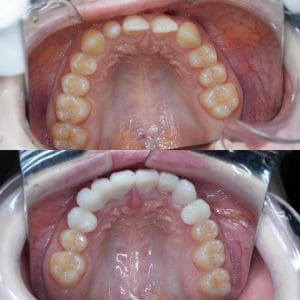

Case022

「歯の長さが短い、歯並びが歪んでる、表面が平面でカッコ悪い、歯茎が腫れている」ということを主訴に来院くださった患者様です。

セラミック矯正は歯科医の技術、センスで仕上がりが全く違うため、審美歯科の中でも担当する歯科医によって最も大きな差の出る診療です。

また、歯並びだけではなく顔貌(お顔立ち)まで綺麗にすることができる診療です。

歯茎の腫れは綺麗に歯を削り直して、正確に型を取り、

精密に作られたセラミックを適合よくセットしてあげることで、前医で入れてから1年以上腫れ続けてた歯茎が1週間で綺麗なピンク色に治りました。

形や並びに関しても、まず歯科医師が「どのような形にするか、どのように並べるか」をイメージしながら綺麗に削ることから始まります。

患者様の主訴通りに綺麗にできて喜んでいただきました。

当院では、患者様の主訴と、治療にかけられる費用、期間によって、ワイヤー矯正、インビザライン、インビザラインGo、セラミック矯正の中から治療法の特徴などをお話しし、その患者様に最適な治療を提案させて頂いております。